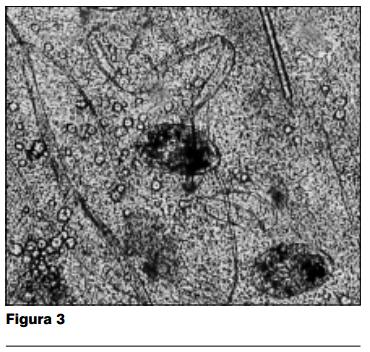

Paraclínica: el examen directo en fresco con KOH al 20%, entre porta y cubreobjeto del material obtenido por escarificacion de las lesiones, muestra abundante cantidad de Sarcoptes scabiei var. hominis en diferentes estadios evolutivos (figuras 3 y 4). El estudio bacteriológico de las lesiones desarrolló Staphylococcus aureus y Streptococcus beta hemolítico.

Las características semiológicas de las lesiones cutáneas nos llevan a la fuerte presunción diagnóstica de una forma clínica particular de escabiosis, la sarna costrosa. Ésta es confirmada al examen parasitológico por dos hechos: en primer término la enorme cantidad de ácaros en la muestra, y en segundo lugar la coexistencia de diferentes estados evolutivos del sarcoptes en un mismo campo microscópico (figura 4). En las formas habituales de presentación de la escabiosis, el estudio parasitológico muestra muy pocos ácaros, y es excepcional que se pueda visualizar en un mismo campo microscópico al mismo tiempo huevos, formas juveniles, adultos y restos parasitarios. Sin duda, esta elevada proliferación de ácaros es responsable de la alta contagiosidad de esta forma particular de sarna, así como de las epidemias intrahospitalarias y en el seno de las colectividades que es capaz de producir (12).